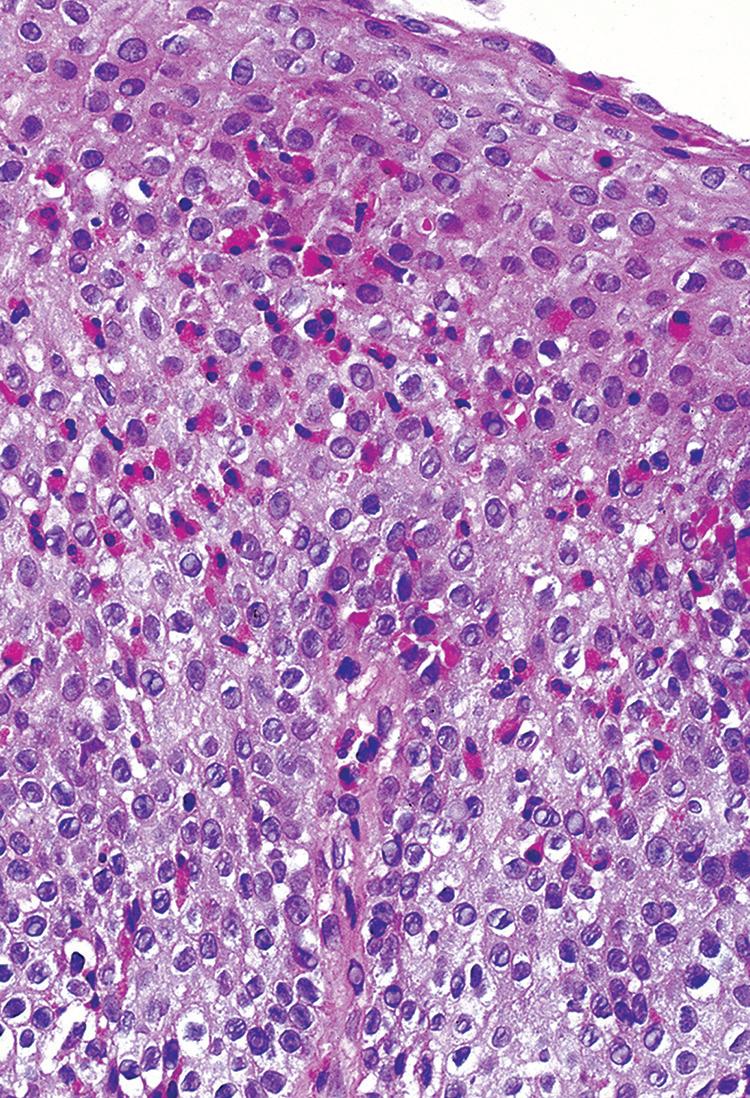

Esophageal biopsies may show increased intraepithelial lymphocytes, especially in pediatric patients (Fig. 1.11).

Well-formed, non-necrotizing epithelioid granulomas may also be present. Active inflammation consisting of intraepithelial neutrophils, erosion, or ulceration can be seen.

FIGURE 1.11

Crohn’s disease. inflammation is predominantly lymphocytic with a few eosinophils and dyskeratotic keratinocytes.